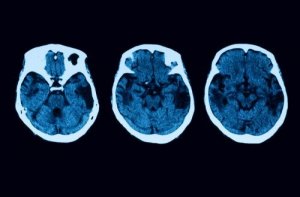

- Beginning of dementia: A person with this condition will present hypometabolism and hypoperfusion that can be detected thanks to a test that involves a neuroimaging study. However, note that dementia arises when the disease is in fairly advanced.

However, diagnostic tests don’t end there. To clear any doubt, there’ll be other neurological tests such as MRIs and tomographies. If everything indicates that you might have posterior cortical atrophy, then there are different treatments you can opt for.